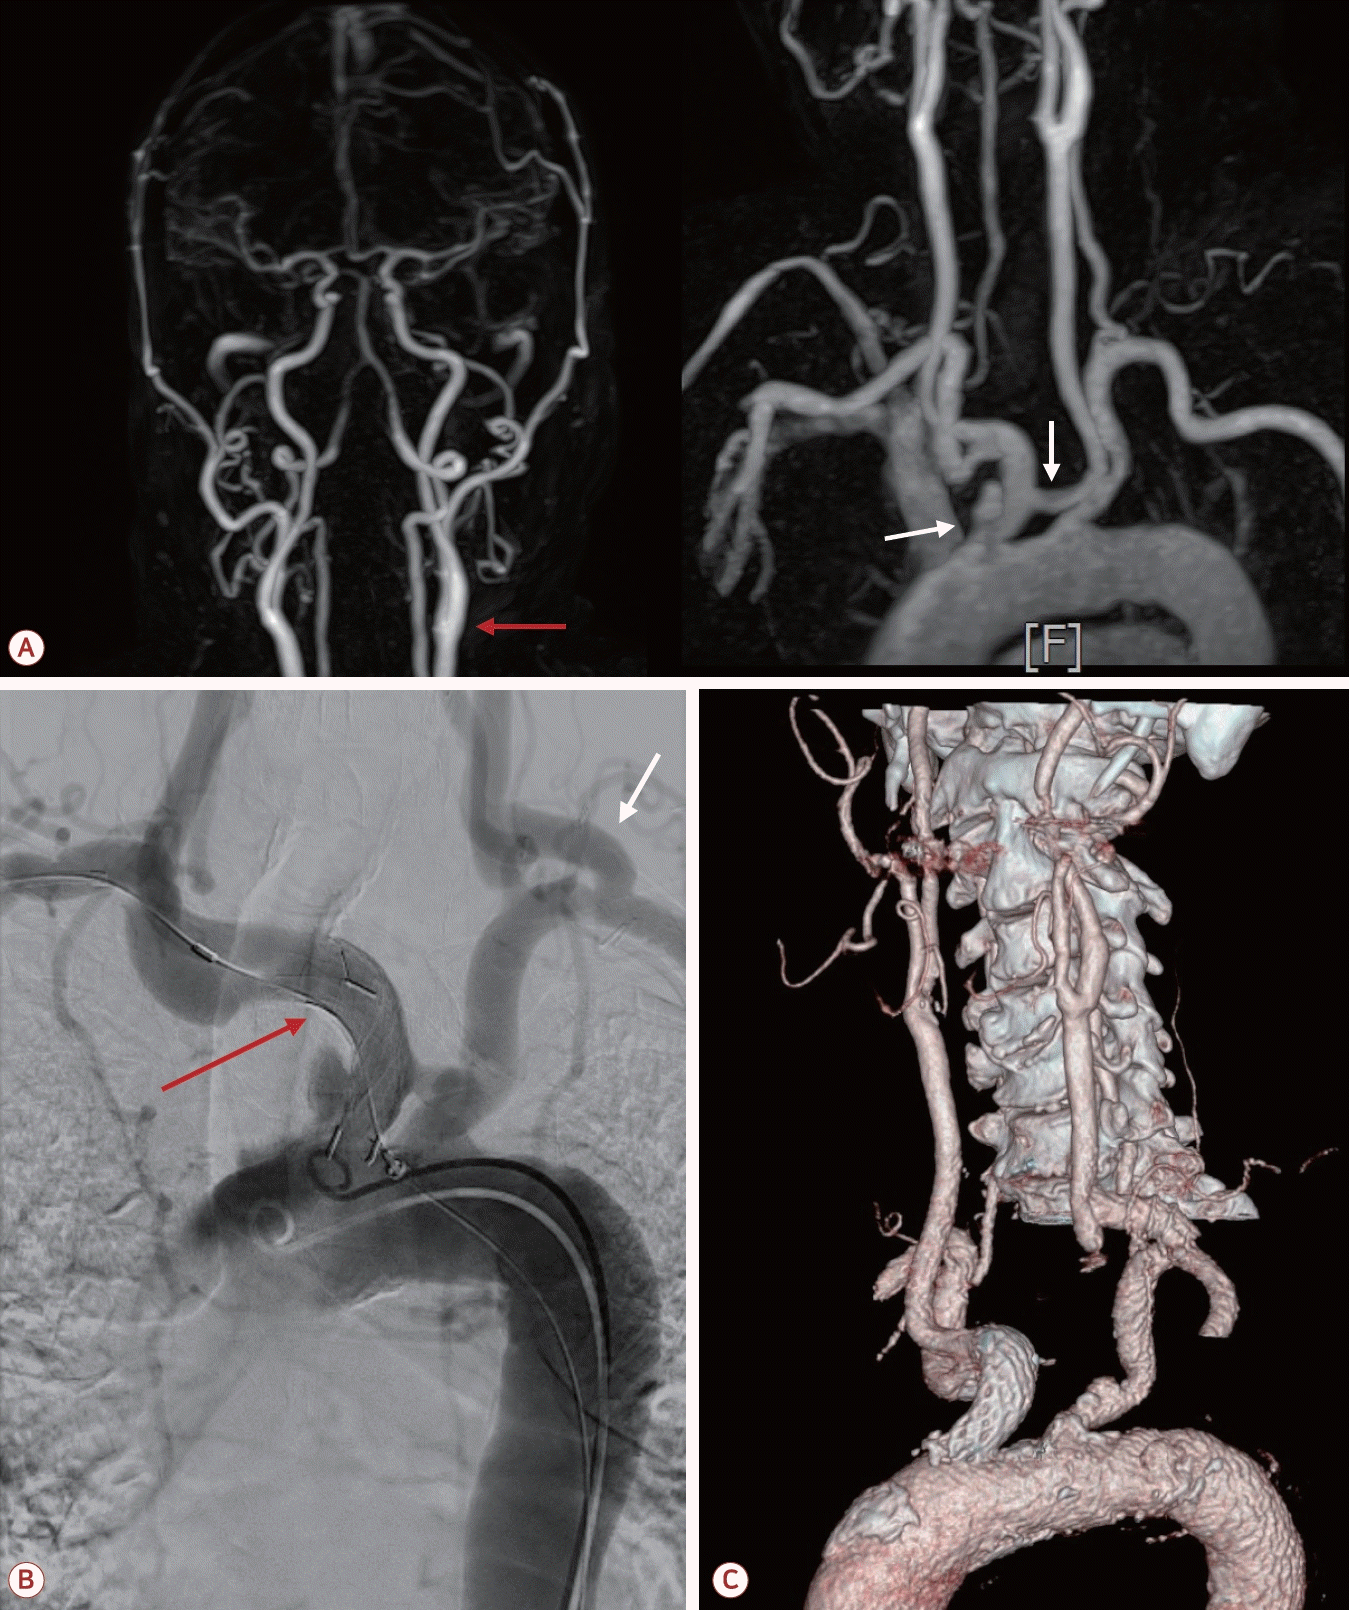

73세 남자가 최근 3개월간 반복적인 허혈뇌졸중으로 내원하였다. 환자는 고혈압, 당뇨, 안정협심증의 기저 질환을 가지고 있었다. 초기 뇌자기공명영상(magnetic resonance [MR] imaging)에서 좌측 대뇌반구와 우측 소뇌에 다발성 허혈 병변이 관찰되었으며(Fig. 1-A) 혈관 검사에서는 좌측 내경동맥근위부(internal carotid artery, ICA)에 76.7%의 협착(NASCET 기준)이 확인되었고 동시에 보바인형 대동맥궁(bovine arch, 공통 기시형 변이)이 관찰되었다(Fig. 1-B). 이에 따라 증상성 중증도 이상의 ICA 협착으로 판단하여 좌측 CEA와 이중 항혈소판 요법이 시행되었다. 그러나 시술 2개월 후에 우측 후 대뇌동맥(posterior cerebral artery, PCA)과 우측 중대뇌동맥(middle cerebral artery, MCA) 영역에 재발성 뇌경색이 발생하였고(Fig. 2-A) 한 달 후에는 좌측 MCA와 PCA 영역에 새로운 뇌경색이 재발하였다(Fig. 2-B). 기존에 진행되었던 두개경유도플러 검사에서 심방중격 결손이나 미세색전 신호를 시사하는 소견은 확인되지 않았고 흉부경유심초음파에서 좌심실 박출률은 정상 범위었으며 3일의 홀터 모니터링에서도 심방세동은 관찰되지 않아 심장성 색전은 배제하였다. 반복되는 색전성 병변의 원인을 찾기 위하여 식도유심초음파(transesophageal echocardiography, TEE)가 진행되었으며 대동맥궁 대만부(greater curvature)에 위치한 7 mm 크기의 궤양성(ulcerated), 유동성(mobile)의 고위험 죽경화판(high-risk aortic arch plaque)이 관찰되었다(Fig. 2-C). 추가적인 머리 혈관조영에서는 기존에 확인되었던 좌측 경동맥의 중증도 협착은 호전 상태를 보였으며 보바인형 대동맥궁 및 팔머리동맥에 동맥류성 확장(aneurysmal dilatation)을 확인할 수 있었다(Fig. 3-A). 이에 신경과, 순환기내과, 영상의학과, 심장혈관흉부외과가 포함된 다학제 협의를 통해 단계적 하이브리드 치료가 결정되었다. 첫 번째 단계로 부분 디브랜칭 수술(좌쇄골하-좌총경동맥우회술[partial debranching surgery, left subclavian-left common carotid artery bypass])이 시행되었다. 수술 한 달 후에 팔머리동맥에 스텐트이식편(endovascular brachiocephalic stent-graft)을 삽입하여 팔머리동맥류의 병적 분절을 제거하였다(Fig. 3-B, C). 스텐트 시술 이후 약 1년 6개월이 지난 현재까지도 환자는 지속적으로 이중항혈소판 요법을 유지하면서 추가적인 허혈 사건 없이 안정적으로 추적 관찰 중이다.

Figure 3.

(A) Additional MR angiography showing the improvement in the previously identified severe stenosis of the left ICA (red arrow) with bovine type aortic arch and brachiocephalic aneurysmal dilatation (white arrows). (B) Angiography imaging showing the debranching status (white arrow) and stent-grafting (red arrow) in the brachiocephalic artery aneurysm. (C) Computed tomography angiography demonstrating the complete revascularization following partial debranching surgery (left subclavian to left common carotid artery bypass) and endovascular stent-graft replacement in the brachiocephalic artery. MR; magnetic resonance, ICA; internal carotid artery.